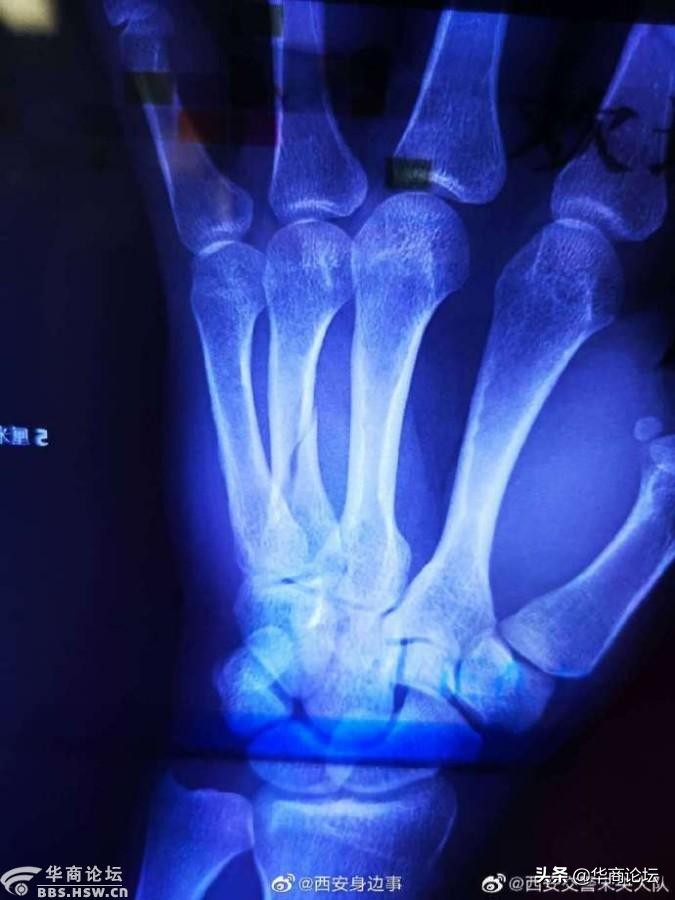

2020年6月9日17时30分许,@西安交警未央大队 大兴分队的民警,在朱宏路与北二环立交桥下执高峰岗,发现一辆大货车无视禁行标志,强行闯入禁行区域。执勤民警见状,立即驱车前去拦截,示意其靠边停车,民警将该车辆成功拦截后,让驾驶员配合民警检查时,司机拒不配合,反而辱骂、推搡执勤民警。

民警再三要求驾驶员积极配合执法,在警告驾驶员无果的情况下,准备将该驾驶员带到警车上做进一步处理。但此时,这名驾驶员的情绪更加激动,不停地辱骂民警,并暴力致使民警受伤,经医生的诊断手臂骨折。最终驾驶员,因涉嫌妨害公务,已被辖区派出所立案侦办之中。